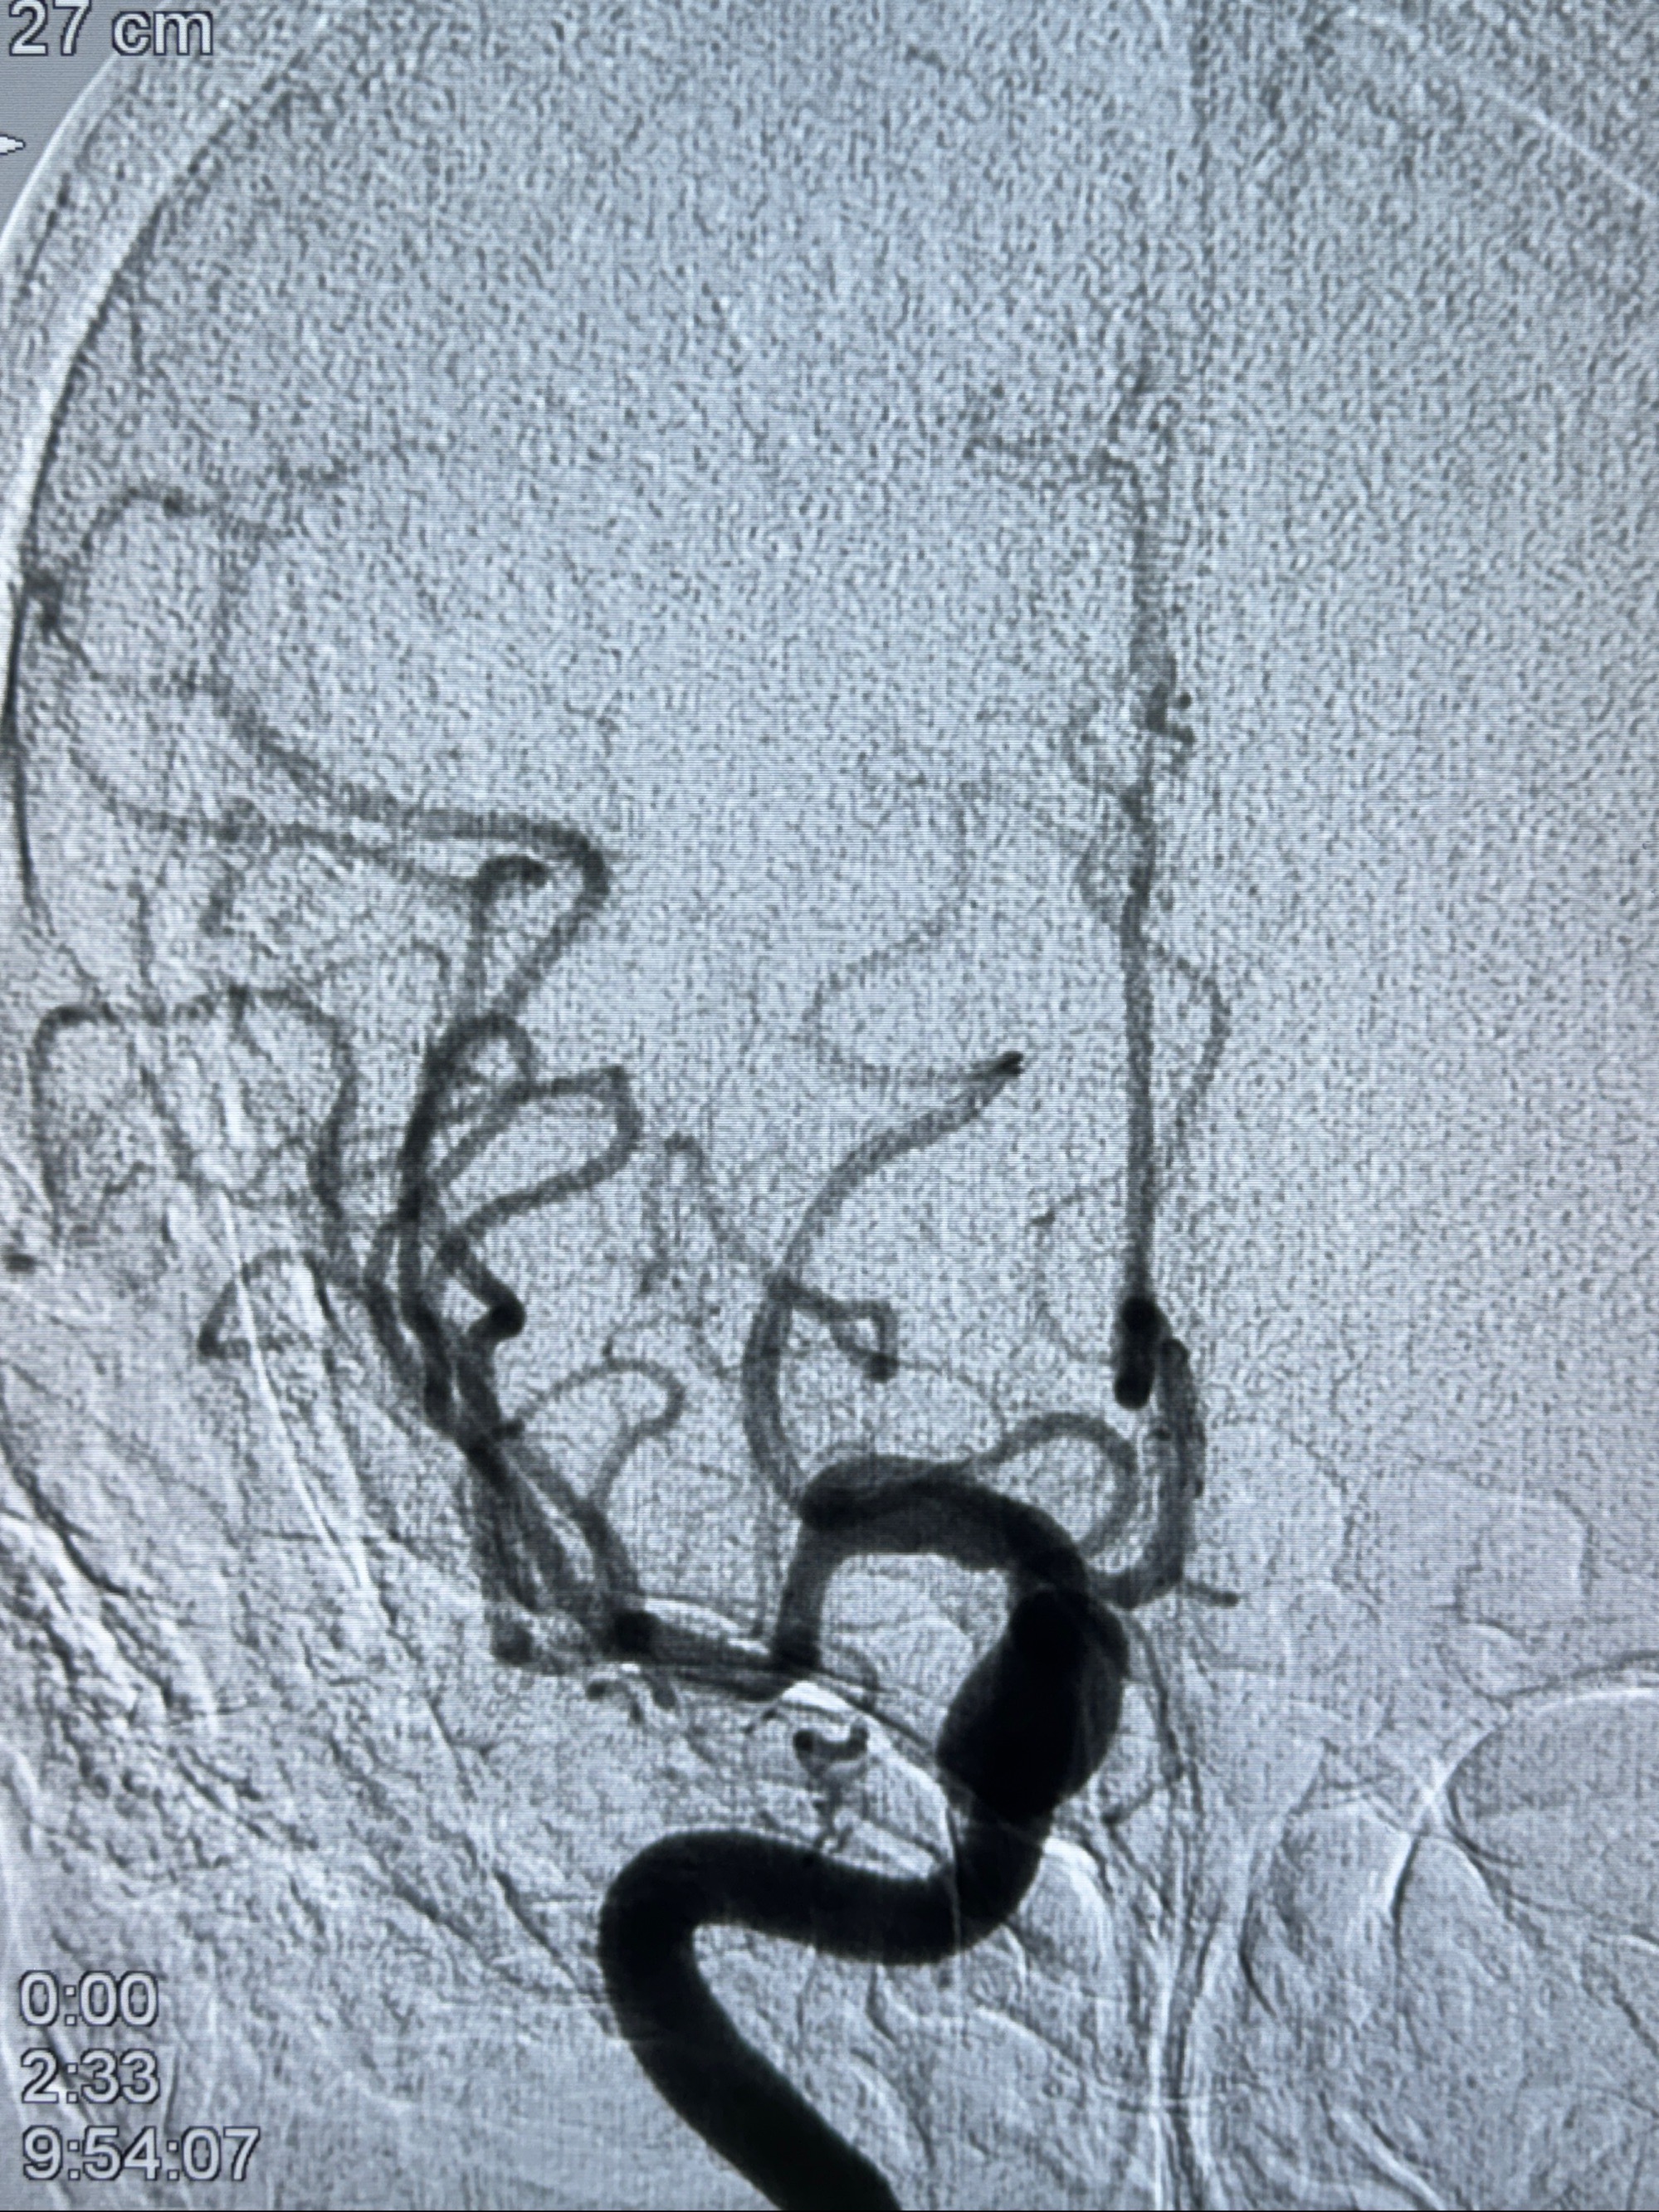

2023-11-24DSA:右侧大脑中动脉下干起始部动脉瘤,约2.3*2.5mm,形态规则

2023-12-04全麻下行支架辅助治疗

S-AB4-20mm